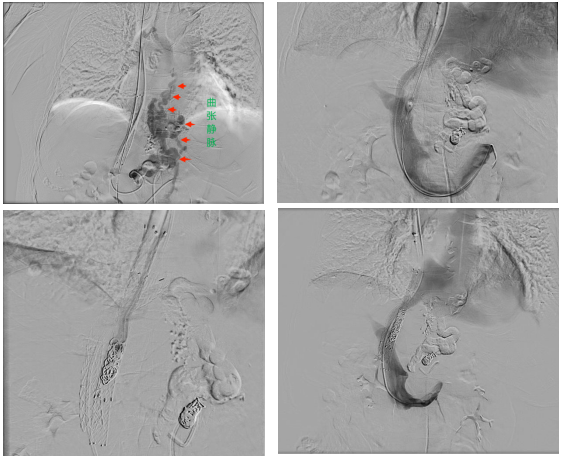

如果说原来的TIPS是第一条“泄洪道”,那么平行TIPS就是在不拆除原支架的情况下,紧邻其旁,重新穿刺、再建一条新的分流道,相当于为淤堵的“生命之河”开辟一条全新的河道。

手术中,在兄弟科室的全力配合下,介入团队精准测量发现何女士门静脉压力梯度高达26mmHg,证实原通道分流量严重不足。随后,医务人员经肝右静脉成功穿刺门静脉右支,在栓塞严重曲张的静脉后,建立了一条全新的8mm分流道。

术后,门静脉压力梯度骤降至7mmHg。为了避免过度分流加重心脏负担,介入团队又巧妙地利用球囊封堵原分流道后反复测量评估门静脉压力后使用弹簧圈封堵原分流道,最终将门静脉压力梯度控制在14mmHg的理想水平。